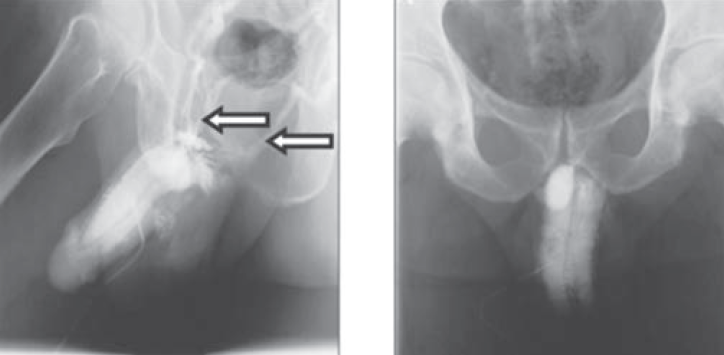

Одним из основных методов диагностики ЭД сосудистого генеза является кавернозография — рентгенологическое исследование сосудов полового члена, во время которого в пещеристые тела через небольшую иглу вводится рентгеноконтрастное вещество (рис. 3). Получаемая рентгенограмма позволяет определить состояние кровеносных сосудов полового члена. При помощи данного метода можно подтвердить или исключить наличия ЭД венозной этиологии, определить уровень сброса венозной крови [20].

Рис. 3. Рентгенологическая кавернозография

Впервые кавернозографию описал в 1946 г. A. De la Pena как способ визуализации вен малого таза [21]. В 1955 г. F. May и H. Hirtl описали рентгенологическое изображение кавернозных тел в норме, а также патологические изменения, которые возникают при травмах, воспалении, опухолях кавернозных тел и приапизме [22]. Современное понимание термина «кавернозография» предложили в 1984 г. R. Virag et al., которые выполнили рентгеновское исследование кавернозных тел после введения вазоактивного препарата папаверина, индуцирующего эрекцию и позволяющего провести визуализацию кавернозных тел в эрегированном состоянии [23]. С помощью динамической кавернозографии можно не только диагностировать наличие патологической утечки, но и определять количество патологических коммуникантных вен, их уровень и бассейн сброса [24]. Фармакокавернозографию обычно выполняют в двух проекциях, она демонстрирует контрастированные венозные сосуды, по которым преимущественно происходит сброс крови из кавернозных тел [25].

Традиционная кавернозография и фармакокавернозография являются диагностическими методами визуализации патологии венозной системы полового члена. Однако, несмотря на относительную достоверность и широкую распространенность фармакокавернозографии, у этого метода существует ряд ощутимых недостатков: использование йодсодержащих контрастных веществ в больших дозах и связанная с этим возможность развития осложнений (аллергических реакций), наличие ионизирующего излучения в высоких дозах. Кроме того, традиционная кавернозография не может быть оцифрована и отсутствует возможность построения трехмерного изображения. При этом частота ложноположительных результатов при использовании вышеперечисленных методик достигает 20–25 % [26]. В современной диагностике, учитывая высокую инвазивность и лучевую нагрузку, кавернозографию часто сочетают с другими методиками. Сочетание кавернозографии с манометрией эффективно для обнаружения анатомических дефектов в первую очередь при веноокклюзивной ЭД [27].

В 2011 г. в Госпитале Красного Креста Такаматсу (Япония) провели изучение нового способа распознавания венозных нарушений эрекции. Авторы исследования использовали методику 3D-обработки изображений КТ полового члена после введения в пещеристые тела рентгеноконтрастного препарата (рис. 4). 3D-компьютерная кавернозография была выполнена 90 пациентам, при этом диагноз ЭД был подтвержден у всех больных. Авторы исследования отметили, что при венозной эректильной дисфункции почти у 92 % пациентов утечка крови происходила в препростатическое венозное сплетение, в которое впадает глубокая дорзальная вена полового члена [28].

Рис. 4. Компьютерная кавернозография